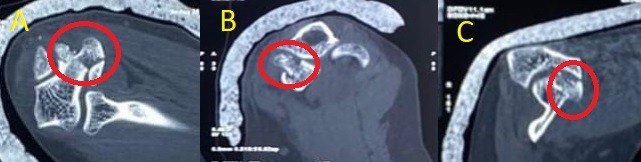

We present the case of a 35-year-old female who presented 3 weeks post-traumatic injury to her elbow. She had a fall on the flexed elbow with force directed through the olecranon tip proximally. She was initially managed with a splint in 90° elbow flexion and forearm supination. She was advised conservative management for the fracture, including immobilization for 8 weeks followed by gradual physical therapy; however, she presented to us due to constant pain and restricted elbow range. On examination, she exhibited swelling and tenderness over the medial elbow without wounds or distal neurovascular deficit. Plain radiographs of her elbow showed a half-moon-shaped fragment displaced anterosuperiorly with irregular ulnohumeral articulation in the lateral X-ray. No dislocation of the elbow joint or the radial head was noted. These findings were corroborated on subsequent computed tomography (CT) scans (Fig. 1 and 2).

Figure 2: Computed tomography scan sections showing the displaced trochlear fragment marked in a circle on (a) axial, (b) coronal, and (c) sagittal cuts.